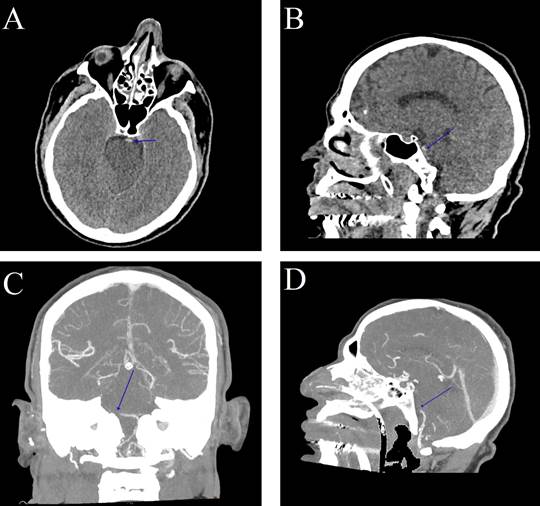

A 30-year-old man had a seizure 30 minutes ago. He developed decreased consciousness associated with recurrent seizures, coarse limb tremors, and fever unresponsive to antipyretics. He is a cocaine user and had been abusing it before the seizures. Axial cranial computed tomography (CT) scan shows a hyperdense artery sign in the basilar artery (Figure 1 A ), and sagittal CT angiography (CTA) detects a filling defect in the basilar artery due to contrast, diagnosing basilar artery thrombosis (Figures 1 B-D ). After imaging, he progressed to loss of oculocephalic reflex, corneal reflex, ciliospinal reflex, and no motor response to painful stimuli. One hour later, in the intensive care unit (ICU), he presented decorticate posturing followed by decerebrate posturing. One day later, the patient died in the ICU.

Figure 1A:  Non-contrast cranial CT in axial view (A) and sagittal view (B) showing the hyperdense artery sign in the basilar artery-basilar artery thrombosis (blue arrow). (B) Cranial CT angiography in MIP (maximum intensity projection) in coronal view (C) and sagittal view (D) showing a filling defect in the basilar artery due to contrast, characterizing basilar artery thrombosis (blue arrow).